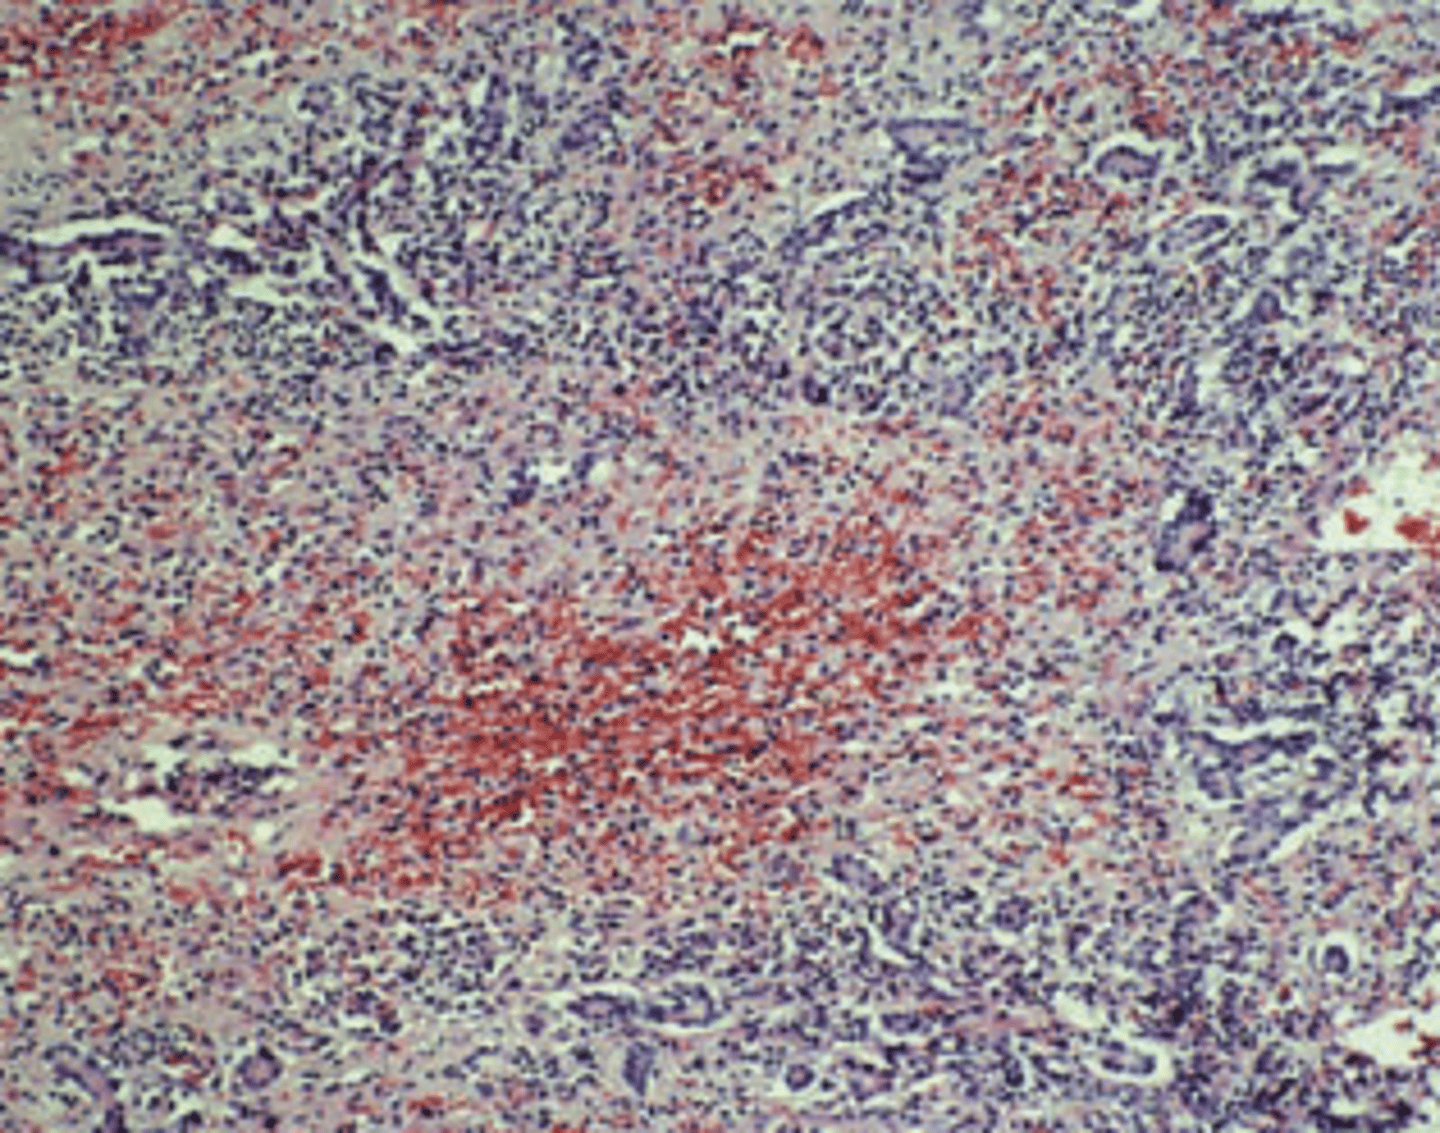

Acute viral hepatitis

A previously healthy 38-year-old man complains of yellow discoloration of his eyes, abdominal pain, and low-grade fever of 1-month duration. Physical examination demonstrates a distended abdomen, right upper quadrant tenderness, and a palpable liver edge 2 cm below the right costal margin. Total serum bilirubin is 7.4 mg/dL. Serum levels of AST and ALT are elevated (229 and 495 U/L, respectively). The prothrombin time is prolonged (18 seconds). A liver biopsy is shown in the image. The arrows point to Councilman bodies. The pathologic findings are indicative of which of the following liver diseases?

(A) Acute viral hepatitis

(B) Alcoholic cirrhosis

(C) Cardiac cirrhosis

(D) Hemochromatosis

(E) Primary biliary cirrhosis